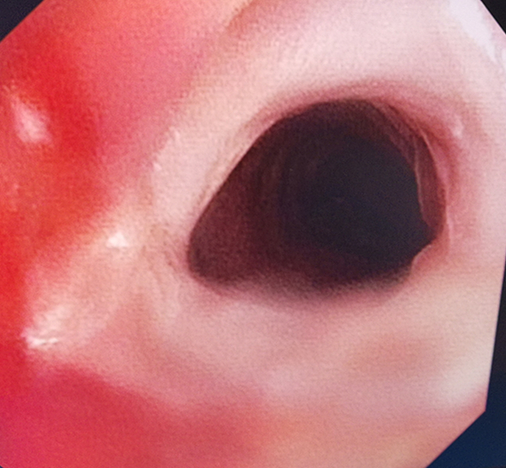

患者因蛛网膜下腔出血行气管切开术,术后气管切开缝合处疤痕增生明显,气管重度狭窄,为有效通气直径约8mm,平静状态下仍呼吸困难。科主任童亚玲、副主任李乾兵组织科室讨论,认为该患者为良性狭窄,植入气管支架后会再次刺激引起疤痕增生,加重气道狭窄,甚至会引起气道闭塞窒息而危及生命,采取球囊扩张术及气管增生组织冷冻消融术对于患者应是最佳选择。

治疗前